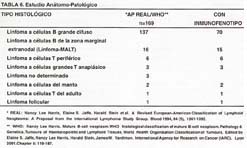

En la Tabla N° 6, se puede apreciar que la variedad histológica del Linfoma Gástrico más frecuente es el Linfoma a células B grande difuso, grupo en el cual algo más de la mitad de los casos ha tenido estudio complementario con inmunofenotipo. El segundo grupo de Linfomas Gástricos de la presente serie corresponde a los Linfomas a células B de la zona marginal extranodal (Linfoma MALT), de los cuales 15/16 han tenido confirmación con inmunofenotipo. Otro grupo de Linfomas como son los Linfomas a células T periférico, a células grandes T anaplásico y a células T del adulto, han tenido en todos los casos evaluación con inmunofenotipo. En menor proporción se encuentran los Linfomas a células del manto, el Linfoma folicular y los Linfomas no determinados.

En la Tabla N° 7, se realiza un análisis comparativo con una serie de Chile que recolecta 132 pacientes de diferentes centros en 23 años (1980 - 2003), lo que nos sirve como elemento de contraste para la presente serie de nuestro instituto con 169 pacientes en 5 años (1,995– 2,000).

Lo primero que vale la pena resaltar es el idioma común empleado en la terminología de ambas casuísticas (46). En general, la serie de Chile, tiene aproximadamente la mitad de sus pacientes catalogados como Linfoma Gástrico, respecto a nuestra serie en la cual 1 de cada 5 pacientes tiene dicho diagnóstico. En el INEN el Linfoma Gástrico es catalogado como cáncer gástrico avanzado tipo Borrmann en el 76.9% respecto a la serie de la Universidad de Chile, con el 35.61%, estando en ambas series el aspecto del cáncer gástrico temprano tipo early en menos del 10% de los casos. Es de remarcar que cuando se refiere al diagnóstico endoscópico del Linfoma Gástrico, la característica predominante en ambas series es la forma de presentación de úlceras múltiples (67.6% en el INEN y 90.41% en la serie chilena). La variedad del aspecto endoscópico tipo cáncer gástrico avanzado no clasificable corresponde al 33.8% en nuestra serie y al 21.8% en el país del sur, siendo la más frecuente en el INEN la forma de cáncer gástrico tipo Borrmann III con el 50% de los casos y en la serie de la Universidad de Chile, 1 de cada 3 pacientes presentan dicha variedad. Si bien los casos del Linfoma Gástrico con aspecto endoscópico de cáncer gástrico temprano tipo early son infrecuentes, ambas series revelan la predominancia de la variedad deprimida tipo IIC.